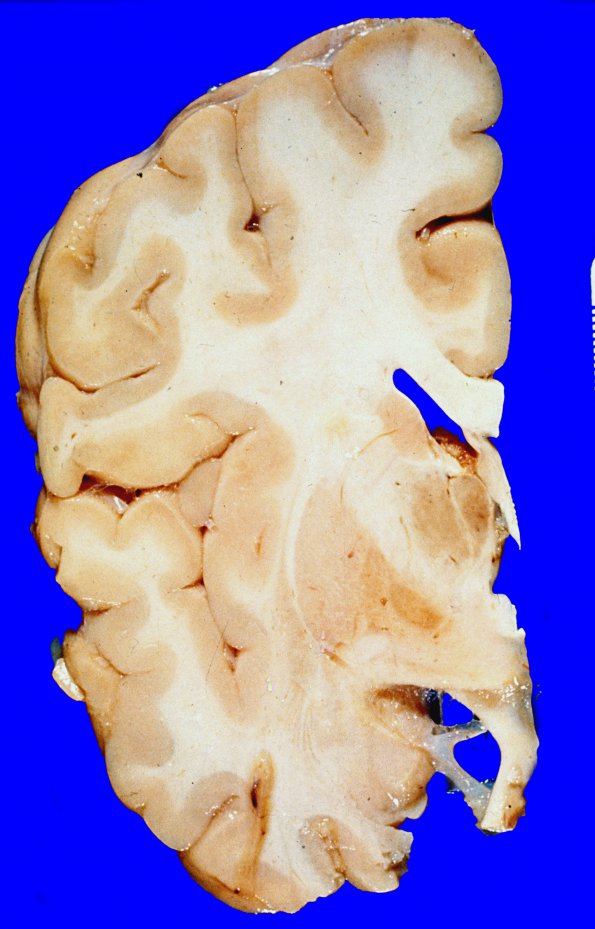

7A1,2 On multiple coronal sections, the cortex appeared as a uniform well demarcated ribbon of tissue of normal thickness . The diencephalic structures were remarkable for the presence of a rusty discoloration of the globus pallidus, primarily in its medial and anterior aspects, but involving the entire limits of this structure. A similar rusty discoloration was not noted in the substantia nigra. However, in this latter structure, there appeared to be a mild amount of uniform depigmentation.